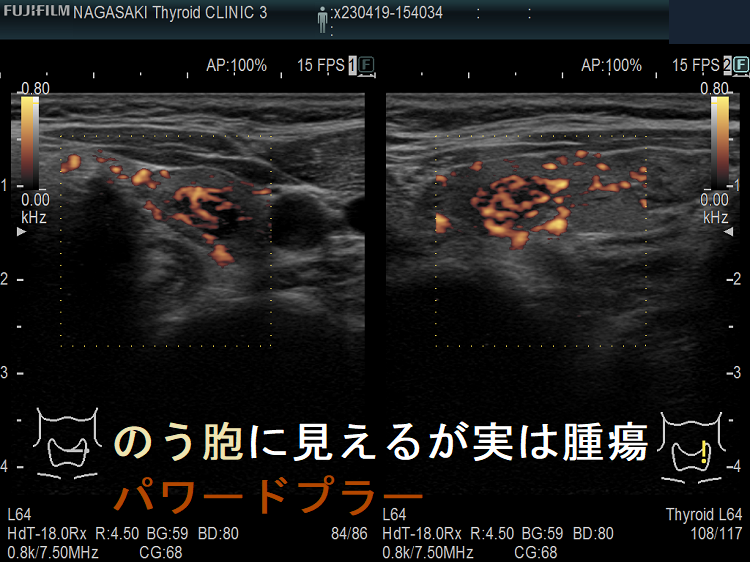

たとえば、通常Bモードでは、

1. のう胞(嚢胞)に見えても、高感度パワードプラーで低流速の細い血管が検出され、実は真っ黒な(極めて低エコーな)甲状腺腫瘍 [甲状腺のう胞(甲状腺嚢胞)に見えるが甲状腺腫瘍]

2. 充実性腫瘍に見えても、高感度パワードプラーで低流速の細い血管が検出されず、実はただの甲状腺のう胞腺腫(甲状腺嚢胞腺腫)(内部の不均質な実質様エコーは粘稠なコロイド物質)

だったなど、臨床診断が覆る場合があります。特に1.の場合は、甲状腺腫瘍甲状腺のう胞(甲状腺嚢胞)と間違えると大変な事になります。極めて低エコーな甲状腺腫瘍は、甲状腺乳頭癌甲状腺濾胞癌甲状腺髄様癌甲状腺悪性リンパ腫の可能性があるからです。

1. ケース①-④ 甲状腺のう胞(甲状腺嚢胞)に見えるが甲状腺腫瘤(結節)・甲状腺腫瘍

2. ケース⑤-⑥ 甲状腺充実性腫瘍でなく甲状腺のう胞腺腫(甲状腺嚢胞腺腫)

甲状腺のう胞に見えるが実は甲状腺腫瘍 パワードプラー

高感度パワードプラーで低流速の細い血管が検出され、甲状腺腫瘍[濾胞性腫瘍]だった。